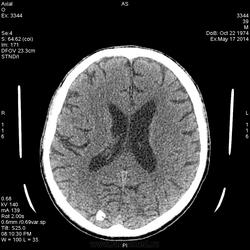

Здравствуйе Уважаемые коллеги! Представляю снимки головы, пациент поступил в приемное с судорожным припадком. Вот что увидел:

Пока написал менингиомы? Будем делать с контрастированием. Я совсем не маэстро в онкологии, поэтому вызывают сомнения данные образования. Жду Ваших мнений.

Тоже не большой знаток: 1. АВМ, 2. паразит. Для менингиом не характерное расположение.

Вот расположение и не подходит для менингиом, поэтому хочу контраст сделать, может прояснит ситуацию

А, что контраст даст при таких обызвествлениях? Возможно посмотреть сосуды и связь с кальцинатами.

Туберозный склероз исключайте